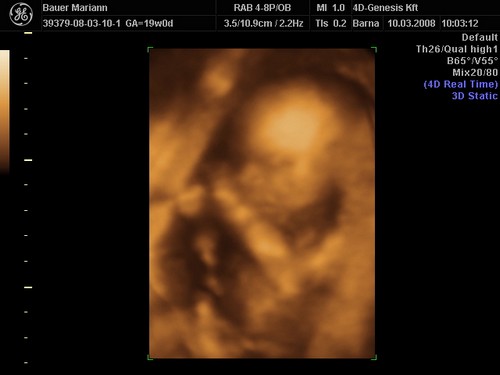

A doki szerint pufók kislány

És egy tappancs 2008.03.08 19:45